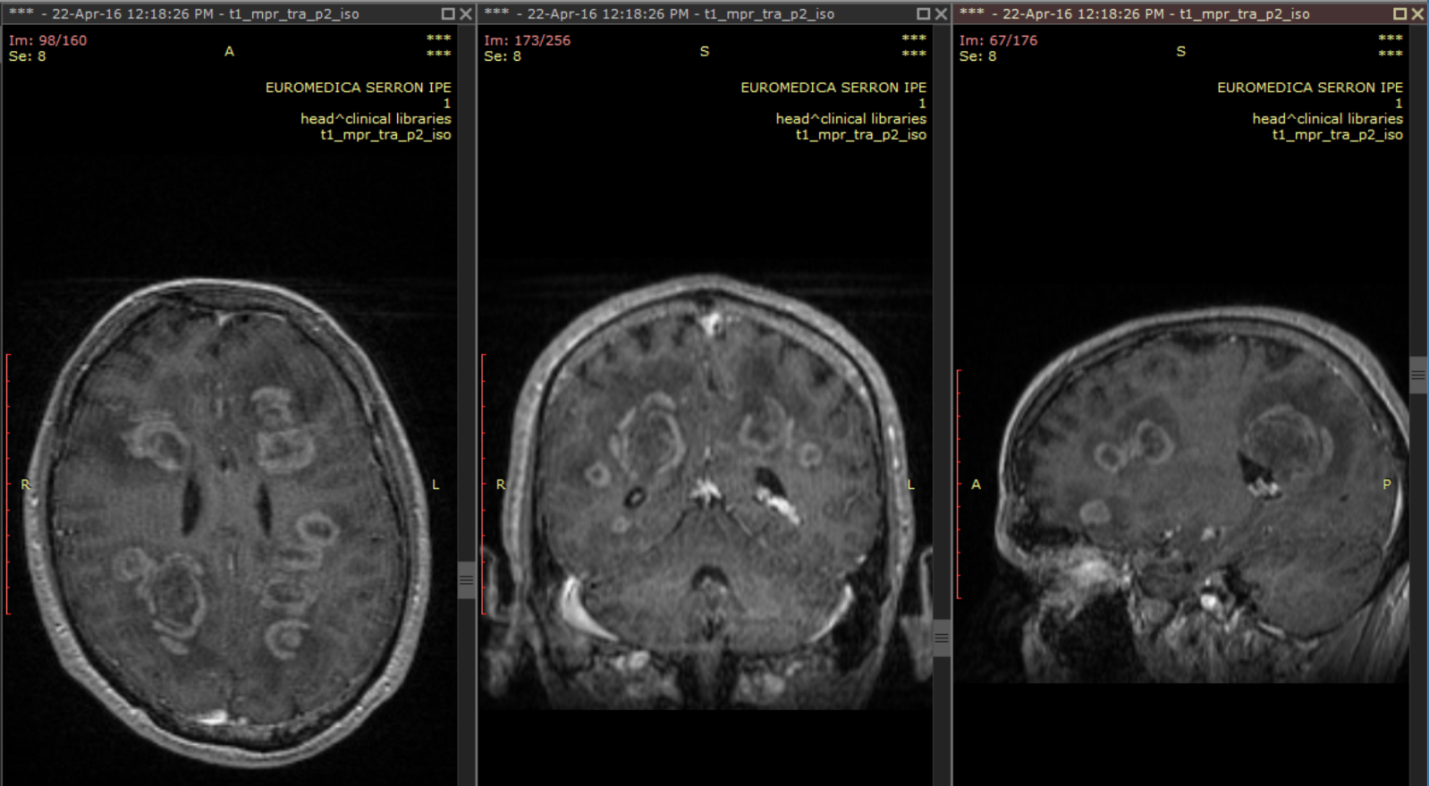

A 38-year old male was admitted to our hospital complaining of progressive memory loss during the last two months. His medical record included heavy smoking (40 pack-years) but was otherwise unremarkable. The results of the neurological examination and laboratory tests were all within normal ranges. An MRI scan of the brain was performed, showing multiple contrast-enhancing space-occupying lesions (Figure 1). The differential diagnosis included brain metastases from some primary tumor such as lung and diffuse multifocal glioma. A thoraco-abdominal CT scan was performed to eliminate the former possibility. Subsequently, a stereotactic biopsy of a single lesion was performed, and the microscopic examination revealed a diffuse astrocytoma, grade II per WHO classification 2007 (Figure 2). At the time of diagnosis, three years ago, we did not perform molecular profiling (IDH mutations, 1p/19q codeletion, ATRX loss, and MGMT methylation status) in central nervous system tumors. Despite the particularly low proliferative index (Ki67: 1-2%), it was decided to be treated aggressively due to high volume disease. He underwent volumetric modulated arc therapy (VMAT) with a simultaneous integrated boost, receiving 54 Gy in 30 sessions with 1.8 Gy per session to the enhancing lesions of the brain and 50 Gy in the peritumoral edema (Figure 3). Concurrent with radiotherapy, he received temozolomide 75 mg/m2. After completing chemoradiotherapy, he continued with adjuvant temozolomide 150 mg/m2 (escalated to 200mg/m2 from cycle two onwards) for 12 months. Since then, he is disease-free with regular MRI/MR spectroscopy imaging (Figure 4). The deterioration of his memory loss halted, and the patient reports no other neurological symptoms.

Figure 1 Brain MRI (T1+Gadolinium) at the time of diagnosis depicting numerous contrast-enhancing space-occupying lesions in a 38 years old male patient with progressive memory loss.